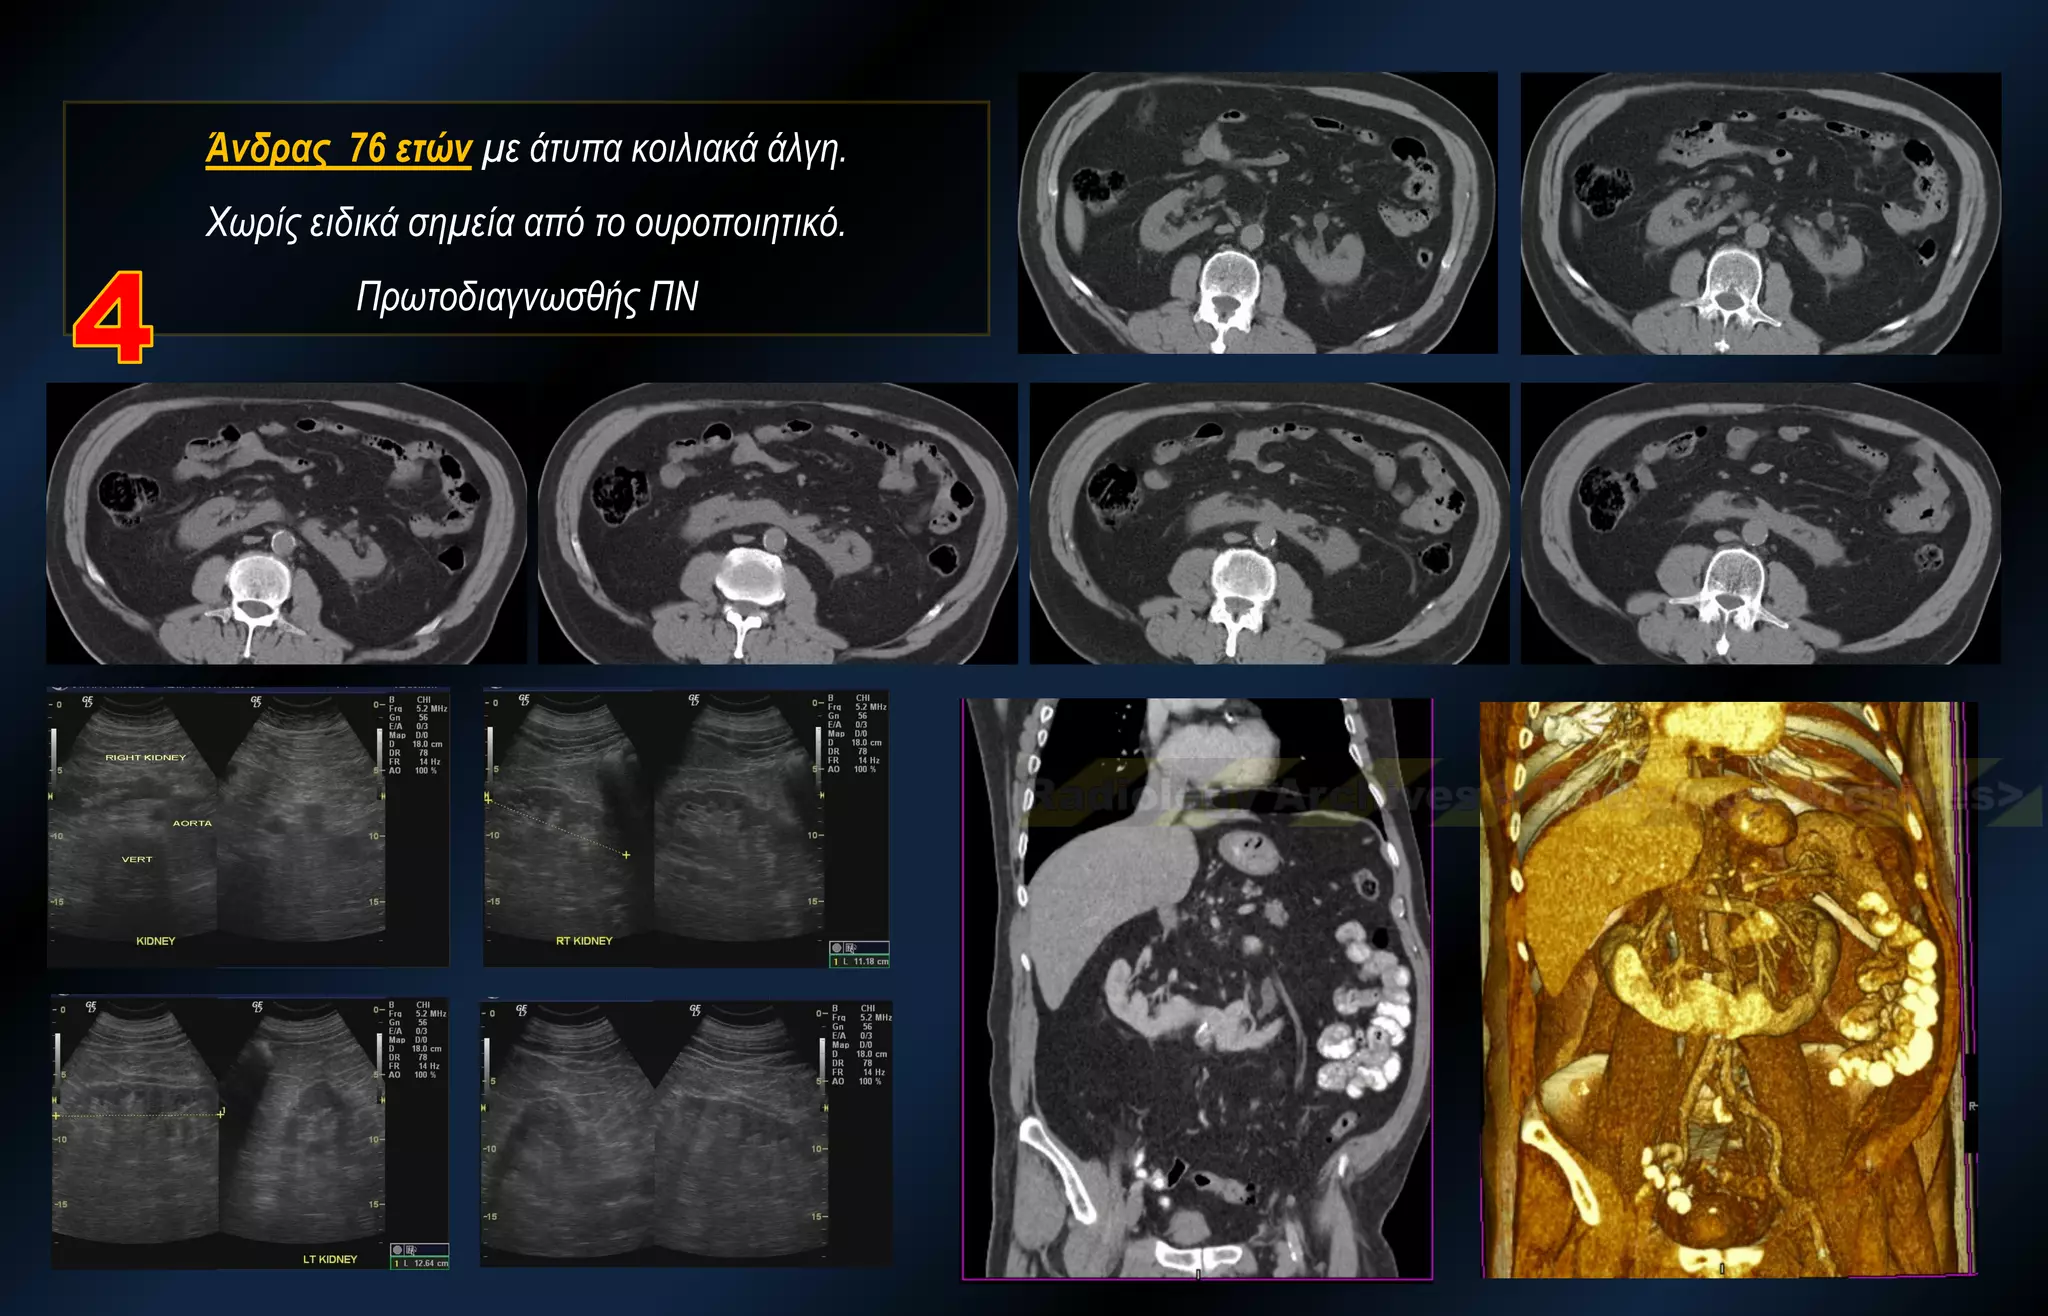

Άνδρας 76 ετών με άτυπα κοιλιακά άλγη. Χωρίς ειδικά σημεία από το ουροποιητικό. Πρωτοδιαγνωσθής ΠΝ

Άνδρας 76 ετώνμε άτυπα κοιλιακά άλγη. Χωρίς ειδικά σημεία από το ουροποιητικό. Πρωτοδιαγνωσθής ΠΝ